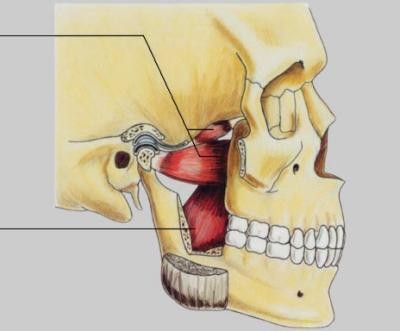

Die Funktionsstörungen des Kiefergelenks stellen eine Herausforderung sowohl an die Patienten als auch an die behandelnden Zahnärzte, Orthopäden, Hals,- Nasen, -Ohren,- Ärzte und die behandelnden Manualtherapeuten dar. Ein Grund dafür sind die vielfältigen anatomischen Zusammenhänge des Kiefergelenks zum gesamten Bewegungsapparat.

Hier spielt die enge Beziehungen zu den Zähnen, der Hals- und Brustwirbelsäule, den oberen Kopfgelenken, den Ohren, zu den angrenzenden Schädelknochen und den nervalen Verbindungen (Hirnnerven) des Kiefergelenks eine wichtige Rolle. Dies macht eine genaue Anamnese und funktionelle Untersuchung und Inspektion des Kiefergelenks, sowie des angrenzenden Bewegungsaparates unumgänglich und zwingend erforderlich. Wünschenswert und sehr wichtig ist dabei die interdisziplinäre Zusammenarbeit zwischen Patient, dem behandelnden Arzt und Therapeuten.